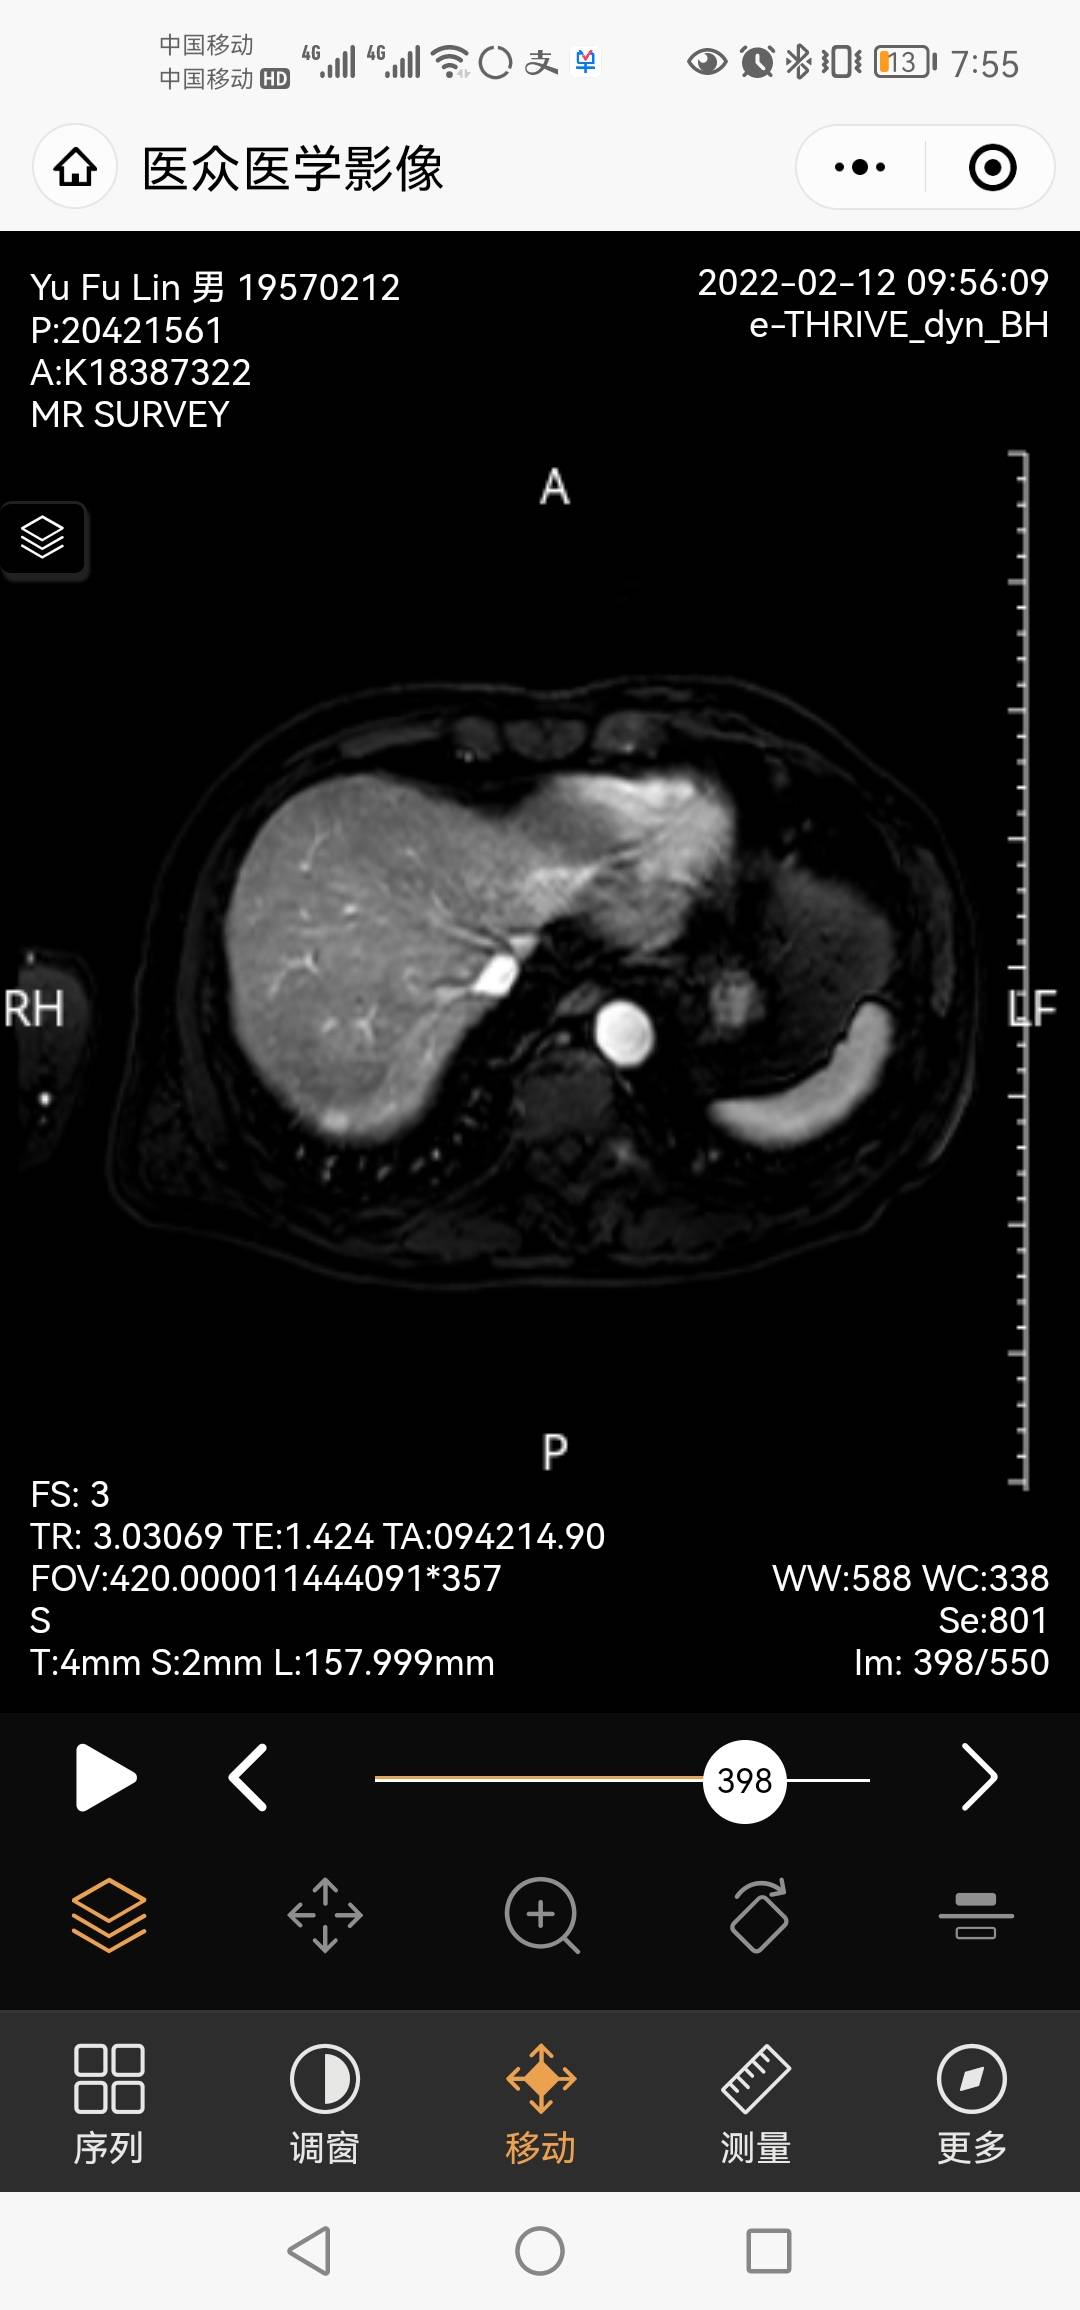

肝转移?

想象过无数次耐药的情景,脑转,骨转,然后也想过有转移就做个基因检测,看看能不能吃三代药,可一旦这样的事情发生,还是觉得有些难过,连续两个月癌胚抗原升高,全身都查了一个遍,最后上腹部核磁结果报告显示有2个囊肿,今天找大夫看了一下片子,她怀疑是转移来的,又要了电子版在手机上放大了看,最后也没给出个肯定的答案,只是说下个月cea在升高,就确定,这个是转移来的,今天联系了基因检测公司,希望能确定可以继续吃靶药,给爸爸多一点时间!我不想这么快就要结束,这些天,我虽然跑的很累,但我也愿意,我会平衡好自己的家,宝宝,工作,还有爸爸!只要你一直能幸运的治疗下去,我愿意用我的生命来陪伴!

另外,有人会看这个肝部的影像么?